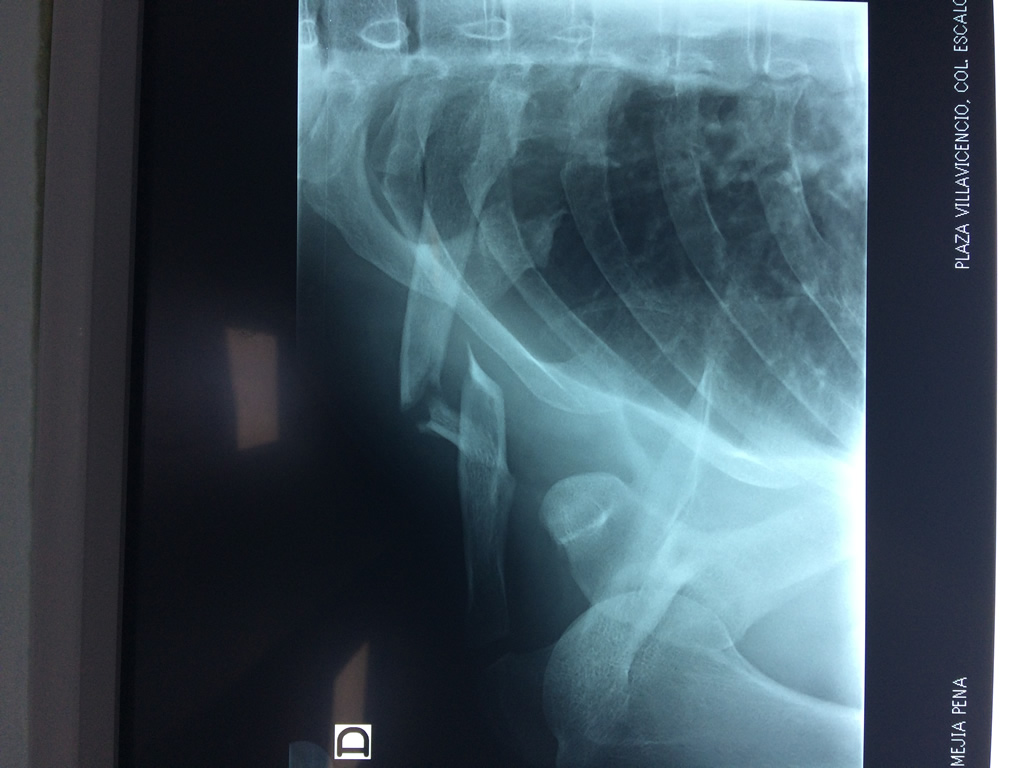

Fémur - Clavícula

La clavícula es un hueso largo, con forma de "S" itálica, situado en la parte anterosuperior del tórax. Junto con la escápula forman la cintura escapular. Se puede palpar por toda su longitud y se extiende del esternón al acromion de la escápula, siguiendo una dirección oblicua lateral y posterior.